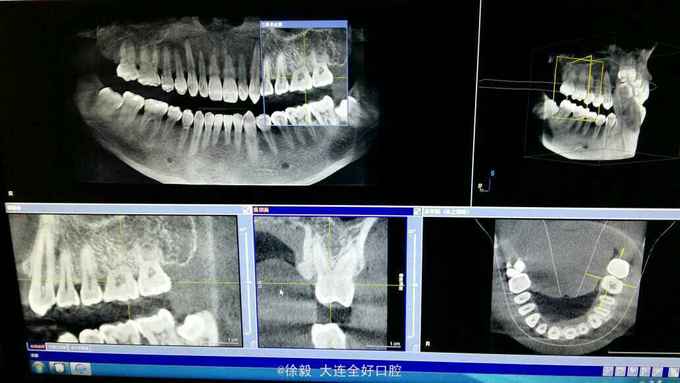

患者男性,40岁,体健。无遗传史。 患者前天就诊洗牙,治疗过程中发现上颌左上34颊侧,67舌侧明显有凸起,手触硬,无波动,无明显疼痛。右侧对应位置也有增生,但是凸起程度小。下颌前牙区舌侧也有黄豆大小凸起。 拍颌面ct和曲断检查,上颌左右45处有明显阴影区,右上45区在映像沙化过程中,骨密度透光变化明显。上颌左右67位置颊侧有致密骨映像,很像骨增生。 患者怀疑有没有恶性倾向,希望会诊一下。